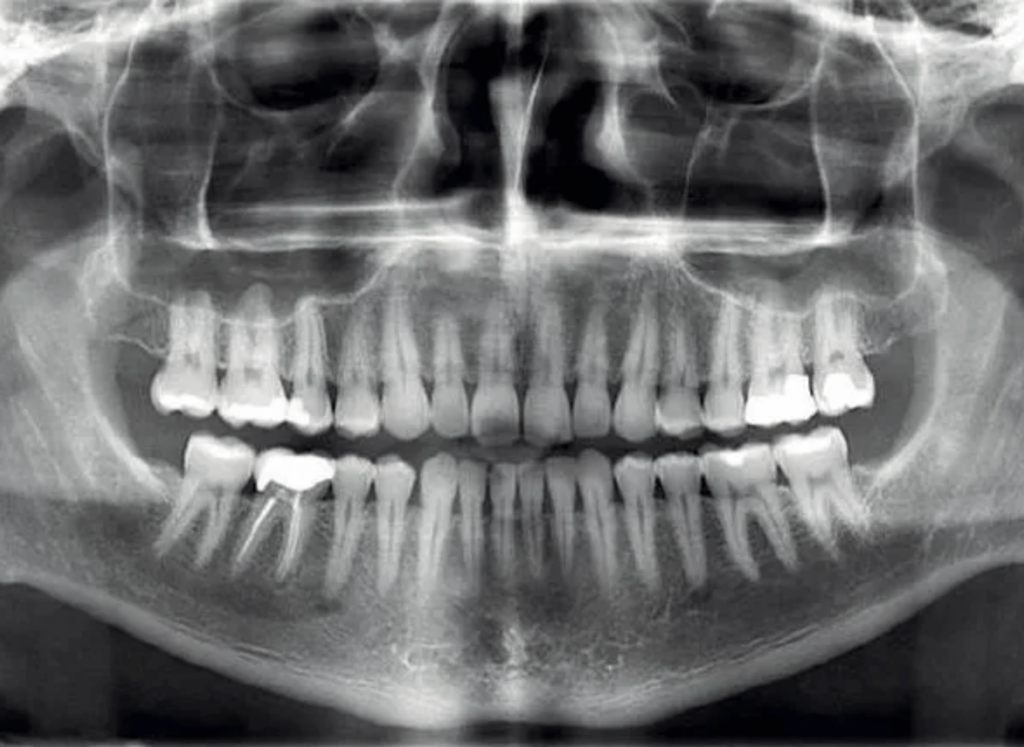

La CBCT es una forma avanzada de tomografía computarizada que utiliza un haz cónico de rayos X para obtener imágenes tridimensionales detalladas de la estructura dental y maxilofacial. A diferencia de las radiografías tradicionales, que solo proporcionan imágenes bidimensionales, la CBCT ofrece una visión completa y precisa de los dientes, huesos y tejidos circundantes. Esto permite a los odontólogos evaluar con mayor precisión los problemas dentales y planificar los tratamientos de manera más eficiente.

Uno de los mayores beneficios de la CBCT es su capacidad para proporcionar imágenes en 3D de alta resolución. Estas imágenes detalladas permiten a los profesionales identificar problemas dentales y óseos que podrían haber pasado desapercibidos con otras técnicas de diagnóstico. Con la información obtenida a través de la CBCT, los odontólogos pueden evaluar la salud de los dientes, la mandíbula, los senos paranasales y otras estructuras maxilofaciales, lo que les ayuda a realizar diagnósticos más precisos.